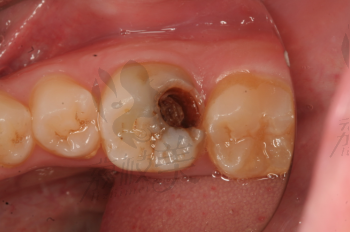

牙齒疼痛是常見的口腔問題之一,而牙爛了個大窟窿晚上痛更是讓人難以忍受,這種情況不僅影響生活質量,還可能引發其他口腔疾病,本文將為您解析牙爛窟窿的原因,并探討應對方法和預防措施。

1、齲齒:齲齒是牙齒爛掉的主要原因之一,長期不注意口腔衛生,細菌滋生導致牙齒逐漸腐蝕。